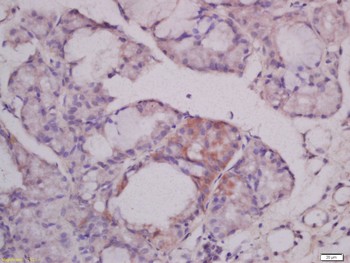

MUC4 Rabbit Polyclonal Antibody

IF, IHC-Fr, IHC-P, WB

应用稀释比例:WB=1:500-2000, IHC-P=1:100-500, IHC-F=1:100-500, IF=1:100-500